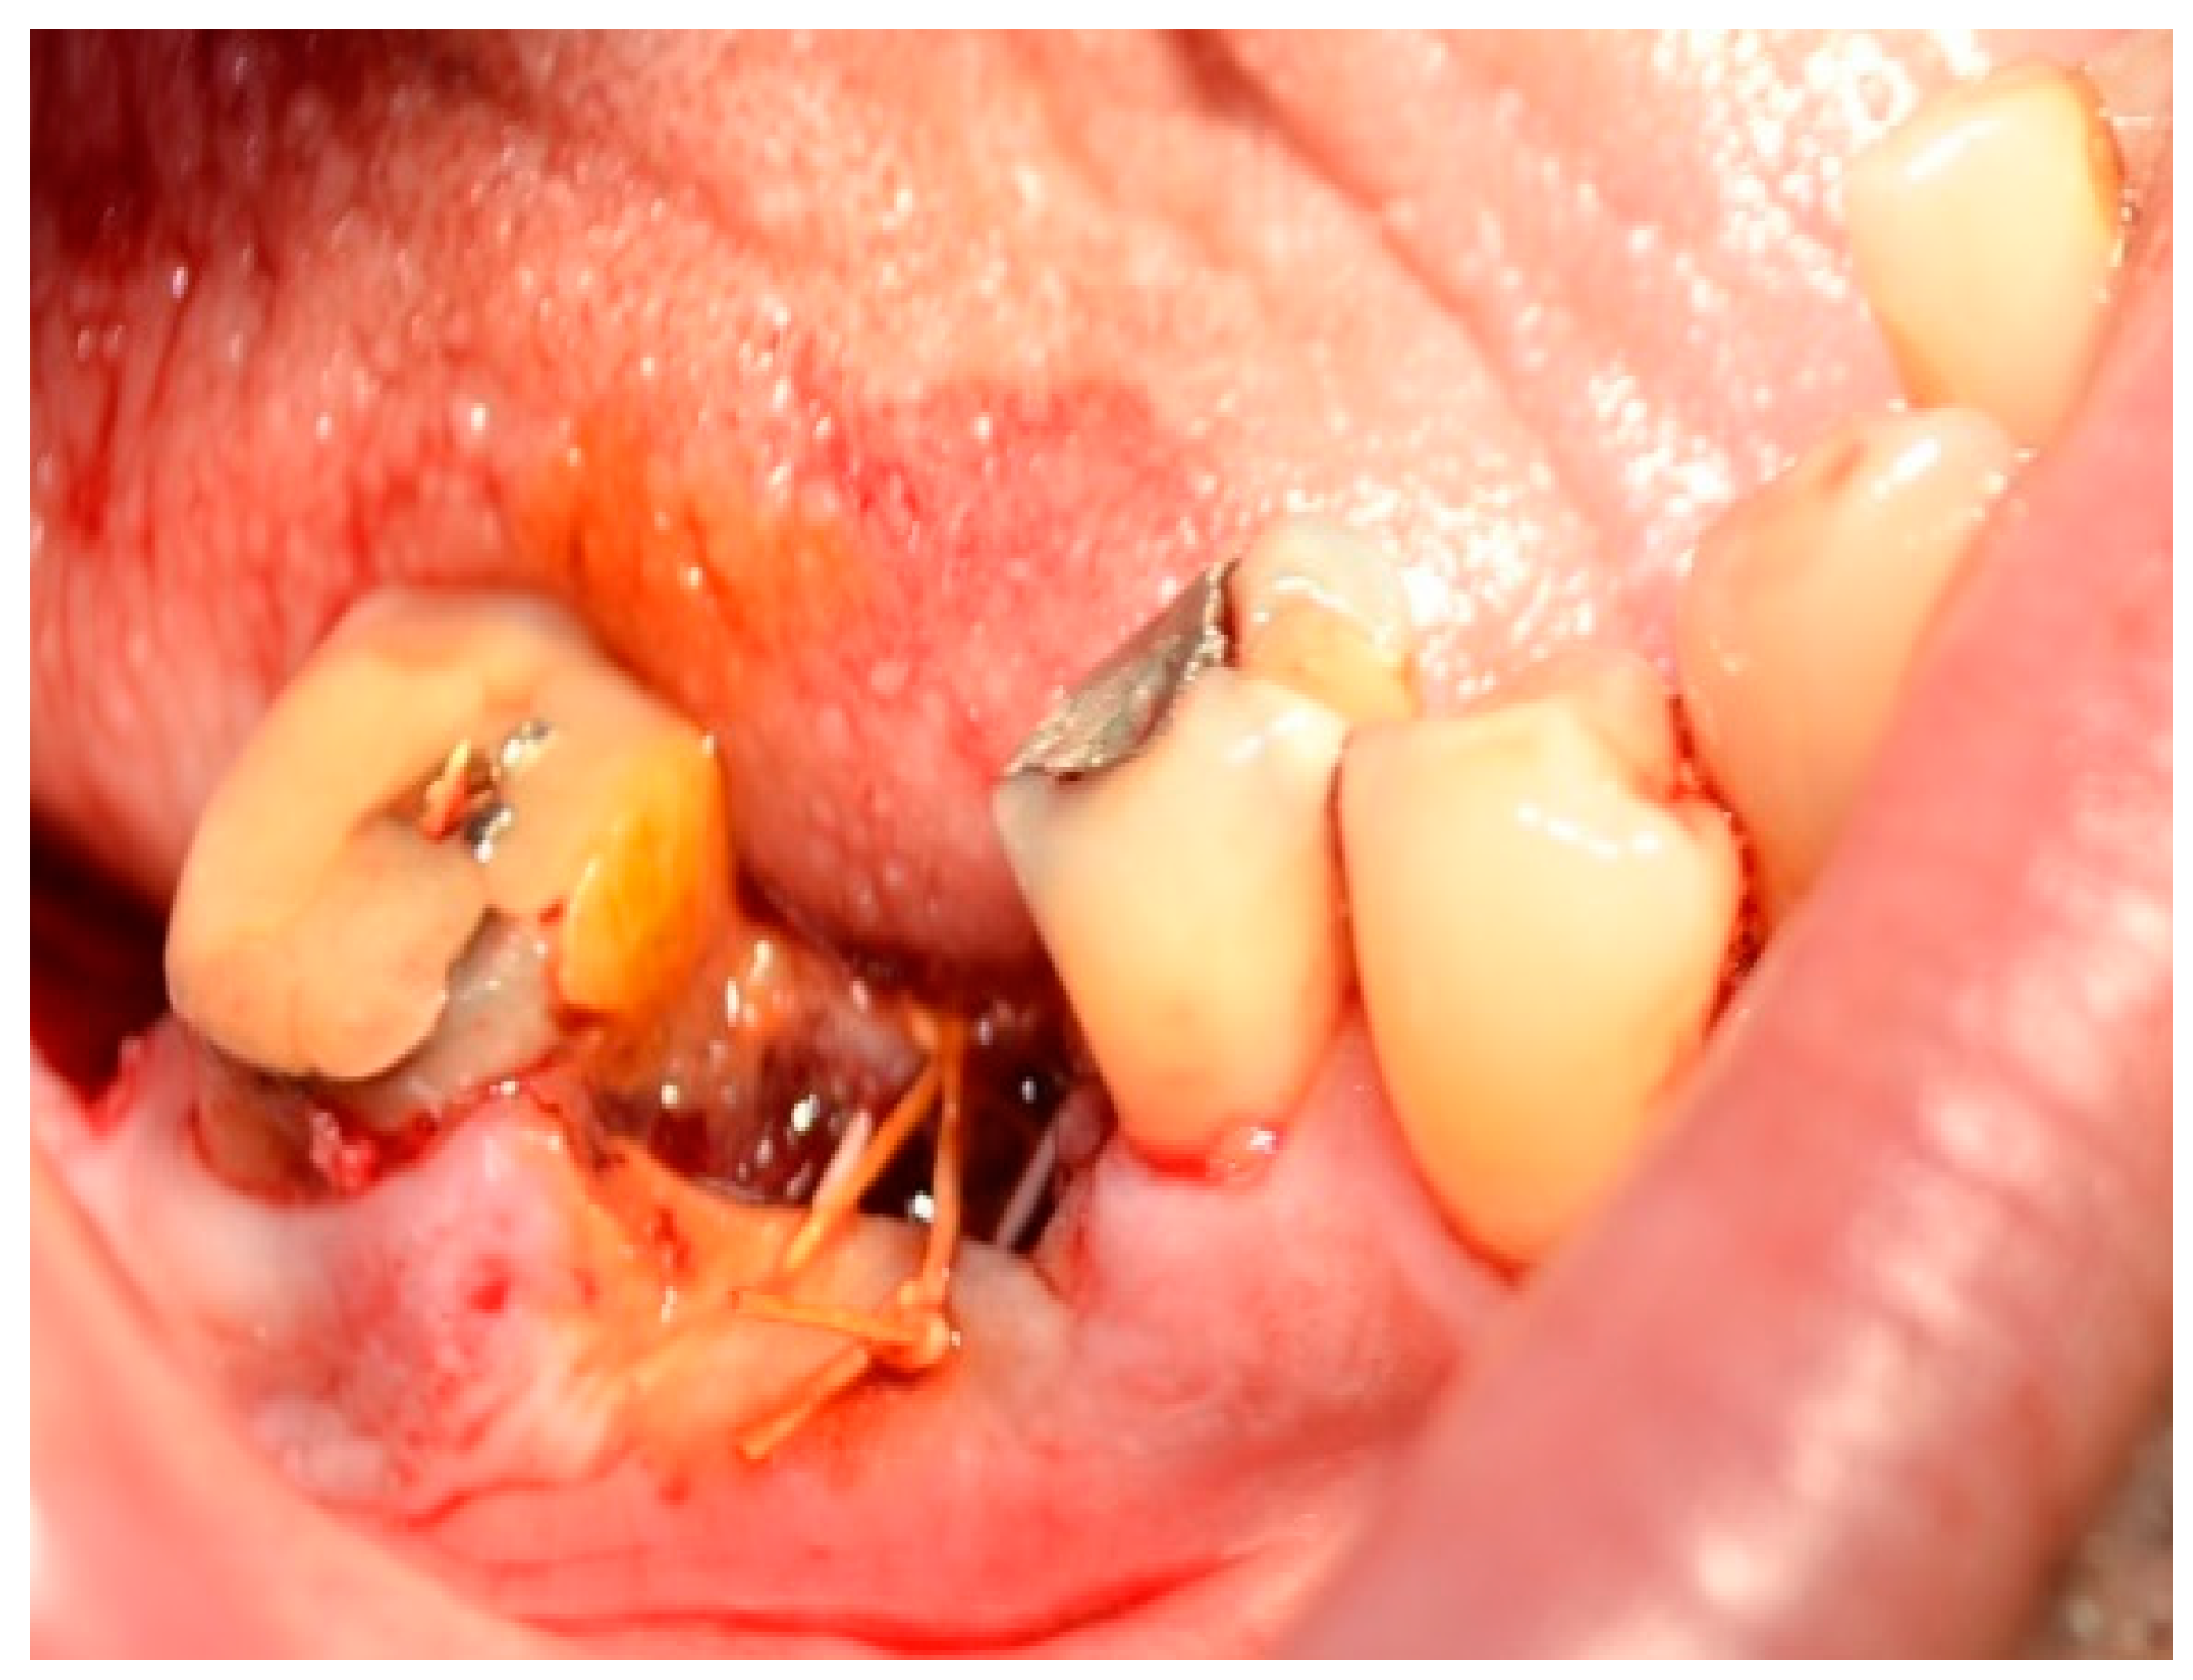

- Systemic disorders related to impaired blood coagulability or diseases of vessel walls (hemorrhagic diatheses) such as hemophilia, hemorrhagic vasculitis, von Willebrand disease, Rendu-Osler disease, and vitamin C and K deficiencies